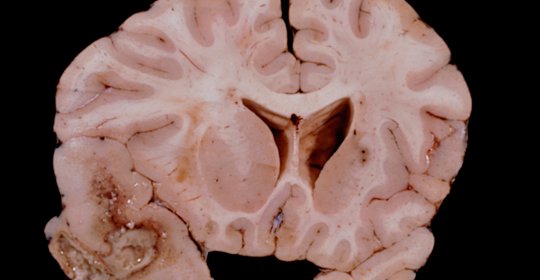

腦動脈硬化血流頻譜改變與供血不足,區別與防治

本文介紹了腦動脈硬化血流頻譜改變和腦動脈硬化腦供血不足兩種不同的病症。前者是由於年齡增長、不良生活習慣、高血壓、高血脂、高血糖等多種原因導致的腦血管結構變化,而後者則是腦動脈硬化的併發症,表現為腦部供血不足的症狀。